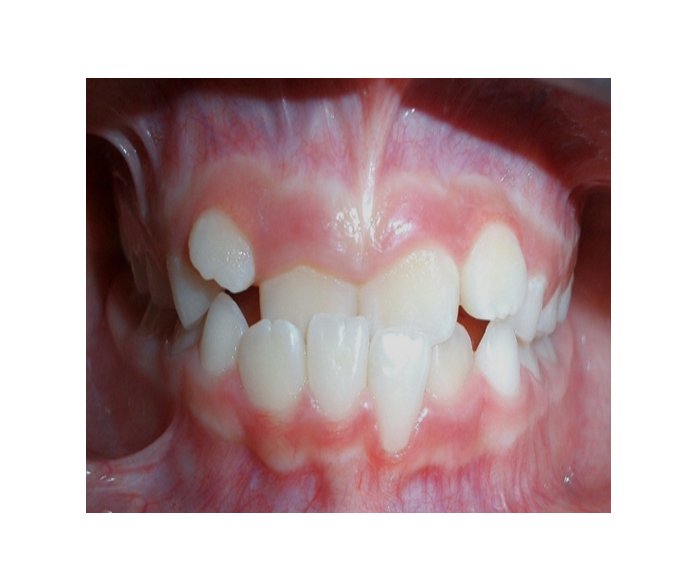

Clase I Protrusión

dental